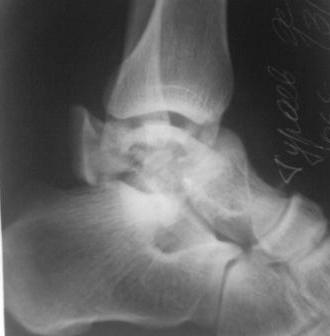

[Ortho] Оскольчатый перелом таранной кости

Поступил  б-ной, 1965г.р., вчера  упал  с высоты. В травм. пункте

произведена репозиция. наложена  гипсовая повязка. Обратился с сильными

болями в  стопе, срочно  рассечена гипсовая  повязка, выраженный

отек стопы, сплошные  фликтены, конечность  уложена  на  шину

Белера, скелетное  вытяжение за  пяточную  кость, антибиотики,

анальгетики, клексан, трентал.

Уважаемые  коллеги, что  делать?

1.Сразу  готовиться  к  артродезу?

2.Или  постараться  открыто  собрать осколки?(тогда вероятность

асеп.некроза большая)

3.Дистракцион.остеосинтез  А.В.Ф.,и дальше  время покажет?

Р-снимки  прилагаются.

Имя     : SP_A0164.jpg